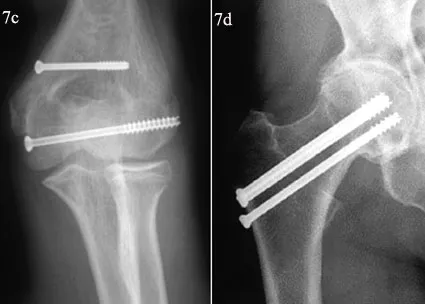

Placas y tornillos

Son placas de metal que se fijan al hueso con tornillos. Las placas se utilizan a menudo para fracturas que involucran múltiples fragmentos de hueso o que están ubicadas en un hueso que soporta peso.